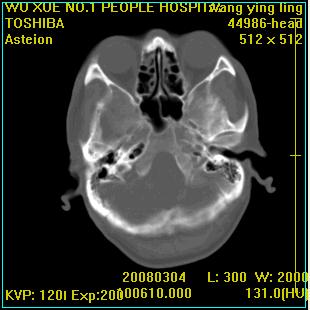

标题: CT12023:女,50岁,头部包块二月,伴轻微头痛,不伴发热。 [打印本页]

标题: CT12023:女,50岁,头部包块二月,伴轻微头痛,不伴发热。

这种病例还是比较多见,起源于颅骨板障,向颅内和颅外生长,考虑血管瘤或嗜酸性肉芽肿,要是有增强ct就好了。

多发溶骨性破坏,骨嗜酸性肉芽肿可能,转移瘤待排除,建议进一步检查。

破坏区边界较清楚,还是考虑良性病变---嗜酸性肉芽肿可能。

颅骨多处破坏伴软组织肿块,考虑为转移瘤可能性大。

病灶呈溶骨性骨破坏,考虑嗜酸性肉芽肿可能转移瘤不除外建议追查病史并进一步检查